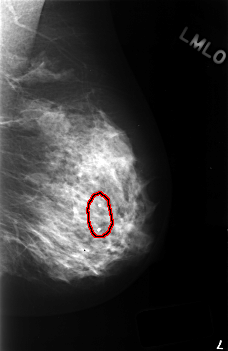

C_0407_1.LEFT_MLO

FILE: C_0407_1.LEFT_MLO.OVERLAY

TOTAL_ABNORMALITIES 1

ABNORMALITY 1

LESION_TYPE CALCIFICATION TYPE DYSTROPHIC DISTRIBUTION SEGMENTAL

ASSESSMENT 2

SUBTLETY 5

PATHOLOGY BENIGN_WITHOUT_CALLBACK

TOTAL_OUTLINES 1

BOUNDARY